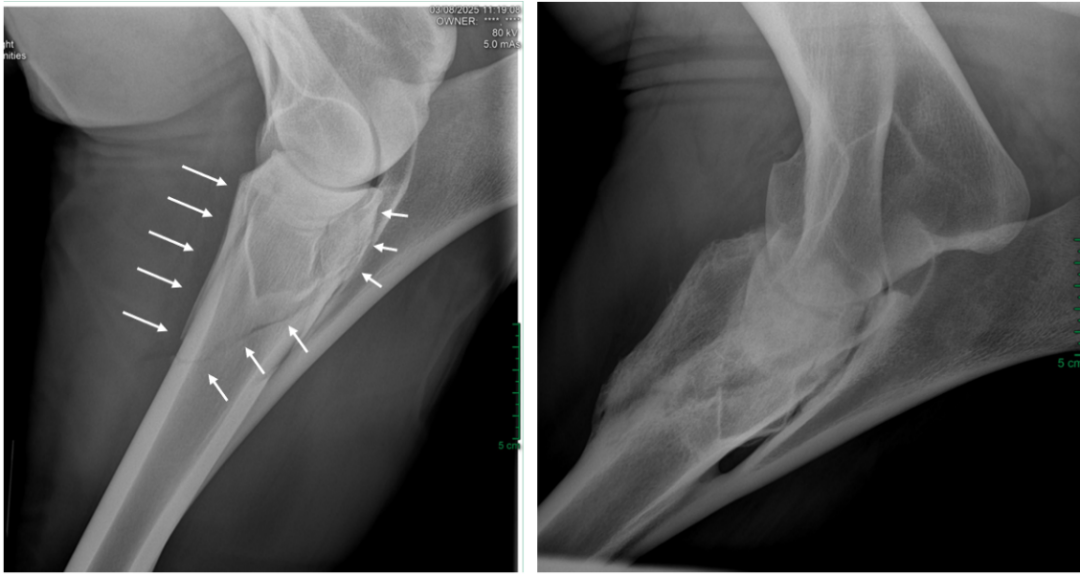

踢伤造成的成年马桡骨骨折,外固定保守治疗,6个月后复查长出骨痂。图源:王炜晗